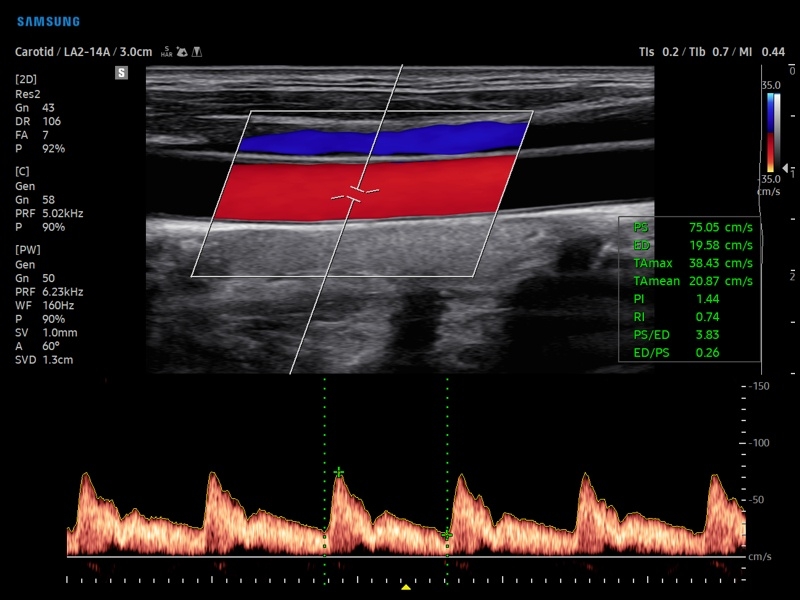

• PW - импульсно-волновой допплер, steering - изменение допплеровского угла в режимах CD и PD, автоматический анализ допплеровских кривых.

• Сонные артерии:автоматическая, полуавтоматическая, ручная трассировка доплеровского спектра; ПСС, КДС, %СтПлощ, %Ст Диам, площадь сосуда, диаметр сосуда, средняя толщина интимы, объемный кровоток.